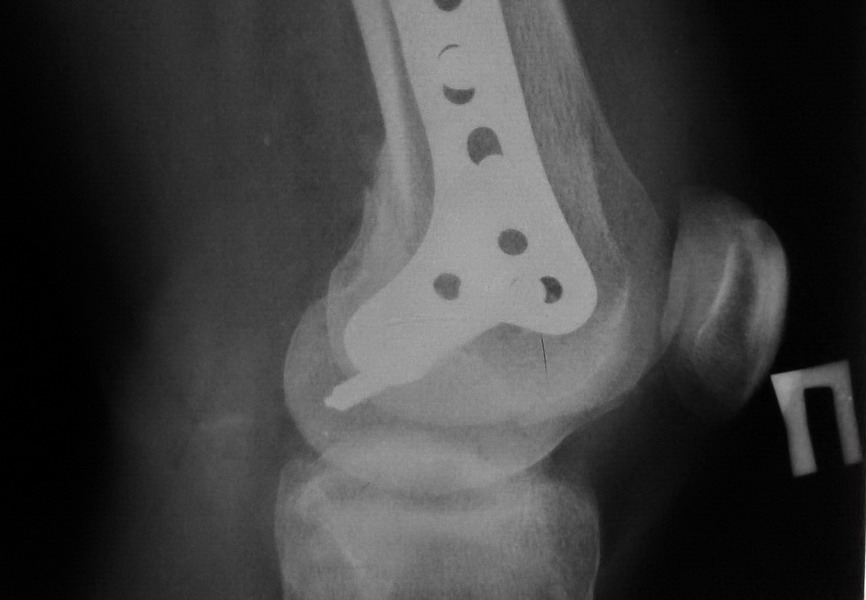

[Ortho] Нелеченный перелом Hoffa

Остеосинтез LCP пластиной